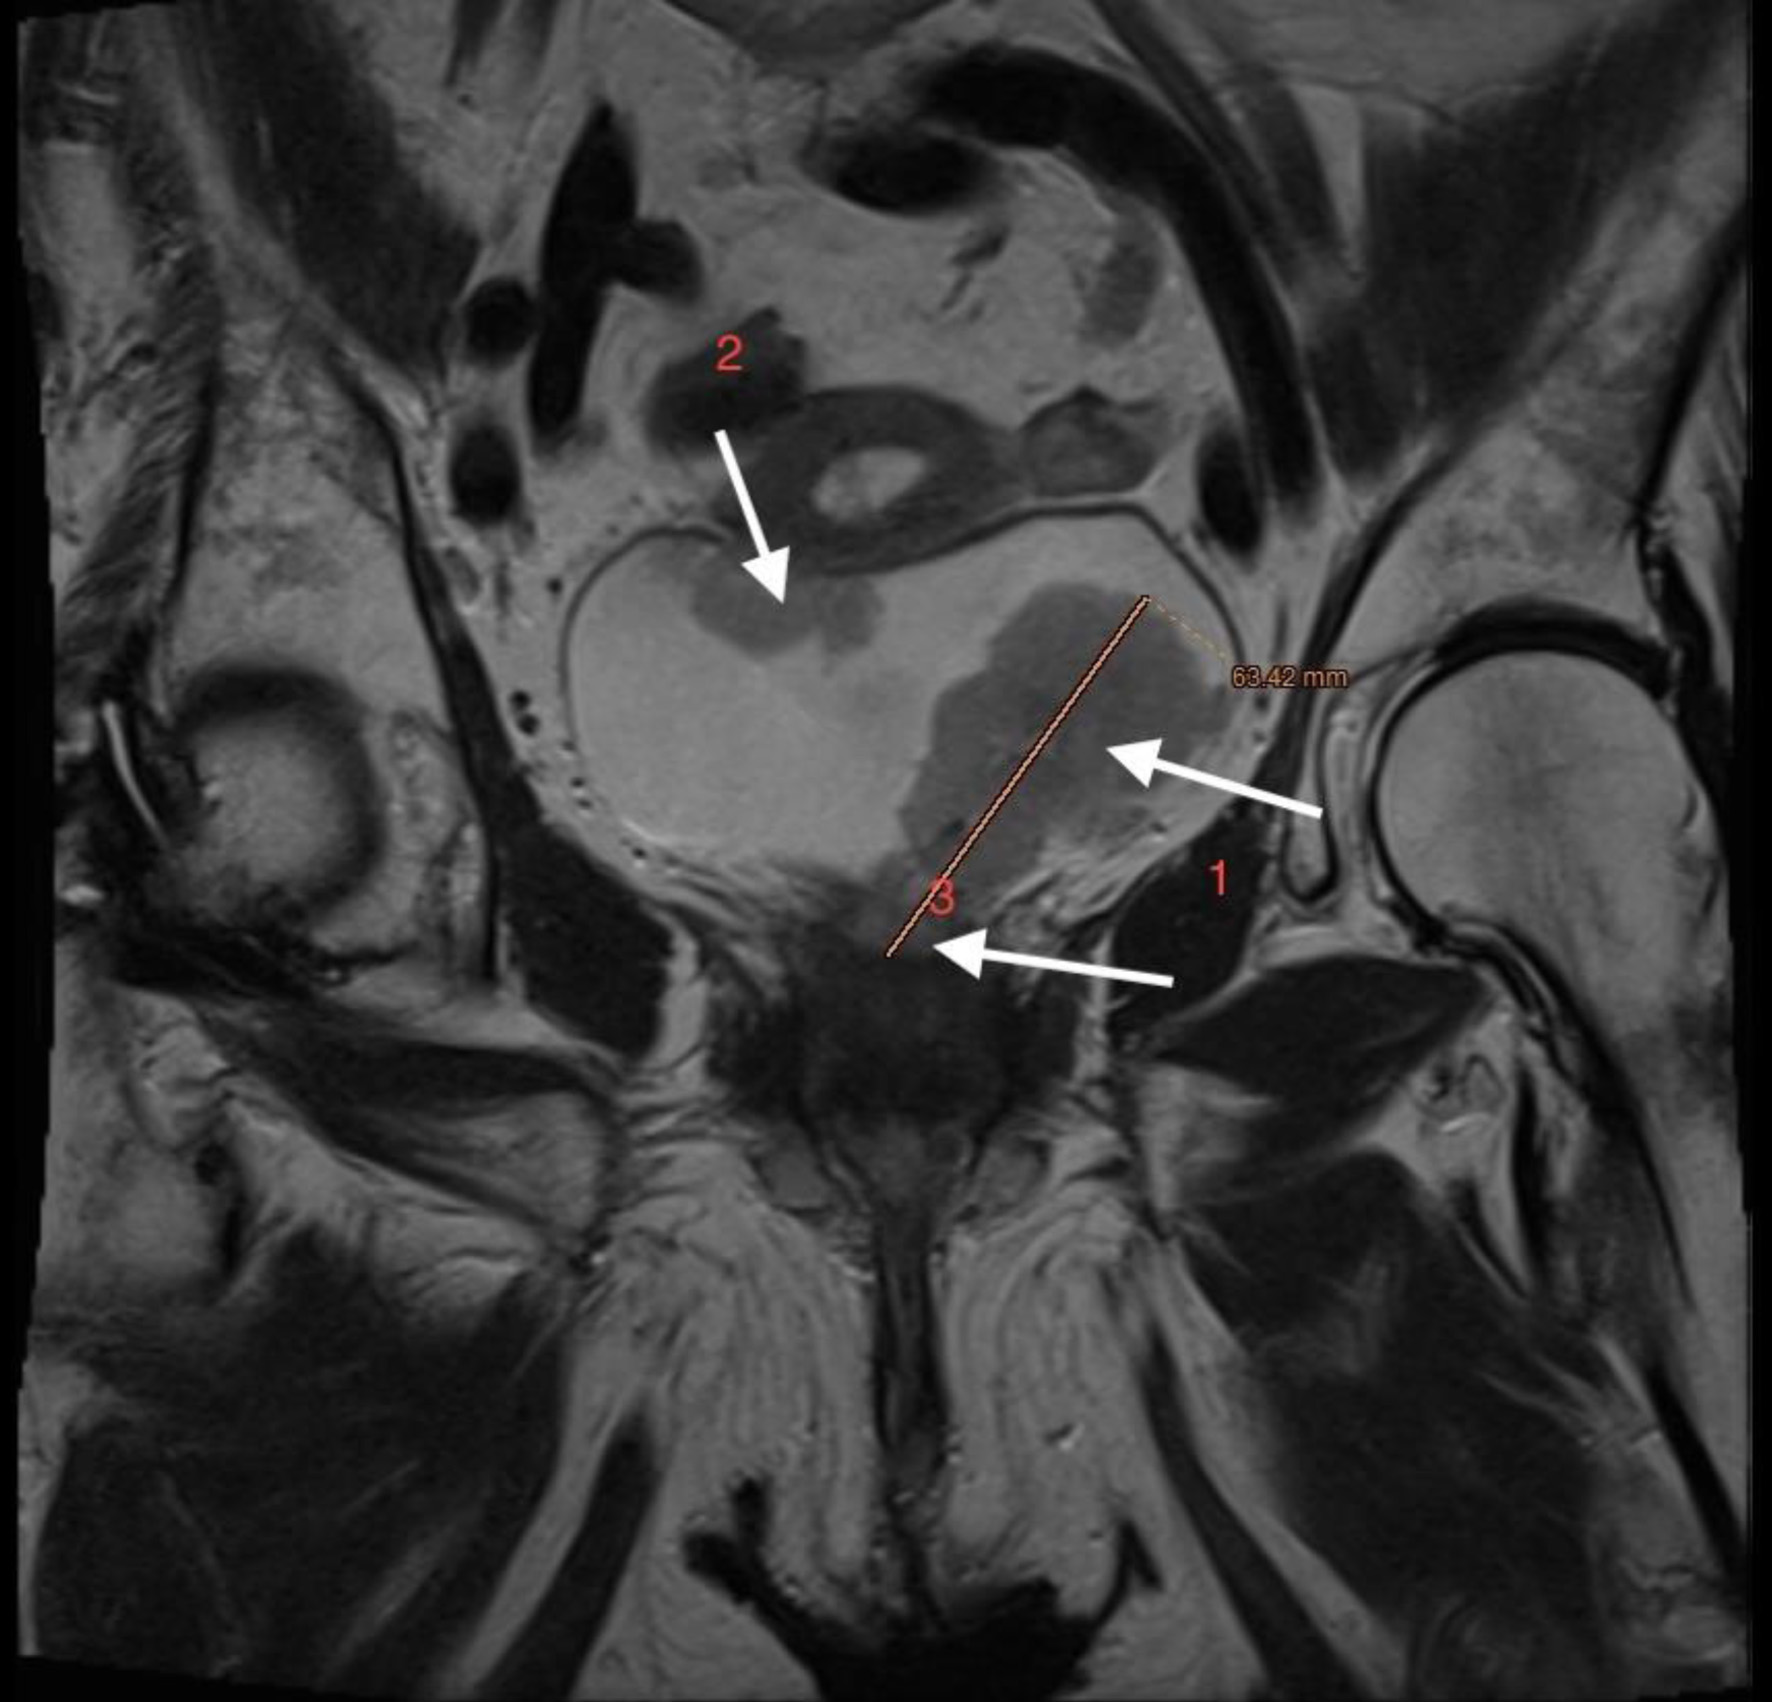

The patient, who had undergone a left nephroureterectomy 1 year earlier for urothelial carcinoma, presented again with suspected malignancy of the right upper urinary tract. Following urological consultation and instrumental evaluation (cystoscopy), urinary bladder tumors were detected, and the patient proceeded to further imaging assessment. Magnetic resonance imaging (MRI) of the upper abdomen revealed a tumor in the right kidney with invasion of the ureter and perirenal adipose tissue (Figs. 6 and 7). Lower abdominal MRI examination confirmed urinary bladder tumors with infiltration of the distal ureter and uterus (Figs. 811). Considering the patient’s clinical status, the potential aggressiveness of the malignancy, the absence of definitive histopathological confirmation of the new tumors (which could represent distinct lesions requiring separate pathological sampling), and the patient’s preference, no preoperative neoadjuvant therapy was administered. Surgery was therefore the only available therapeutic option, to which the patient provided full informed consent, despite her high-risk clinical profile and the complexity of the proposed high-risk surgical procedure. The postoperative histopathological report demonstrated high-grade renal urothelial carcinoma with contiguous extension to the ureter, urinary bladder, and bladder neck. Five of the 11 excised lymph nodes were metastatic, classifying the tumor as pT4N2Mx. Despite radiological evidence suggestive of uterine involvement, histopathological examination of the uterus and ovaries showed no malignancy; instead, polypoid endometrial hyperplasia and ovarian cysts were identified.

Figure 6. Lower abdomen magnetic resonance imaging (MRI) examination demonstrated tumor invading ureter (arrow).

Figure 7. Upper abdomen magnetic resonance imaging (MRI) examination demonstrated tumor invading renal parenchyma (arrow).

Figure 8. Lower abdominal magnetic resonance imaging (MRI) revealed a vegetative, infiltrative lesion invading the surrounding adipose tissue and occupying the urinary bladder cavity (arrow).

Figure 9. Lower abdominal magnetic resonance imaging (MRI) revealed a vegetative, infiltrative lesion invading the surrounding adipose tissue and occupying the urinary bladder cavity (arrows).

Figure 10. Lower abdominal magnetic resonance imaging (MRI) demonstrated an infiltrative tumor involving the urinary bladder and distal ureter (arrows 1 and 2), with extension into the uterus (arrow 3).

Figure 11. Lower abdominal magnetic resonance imaging (MRI) indicated possible infiltration of uterus (arrow).